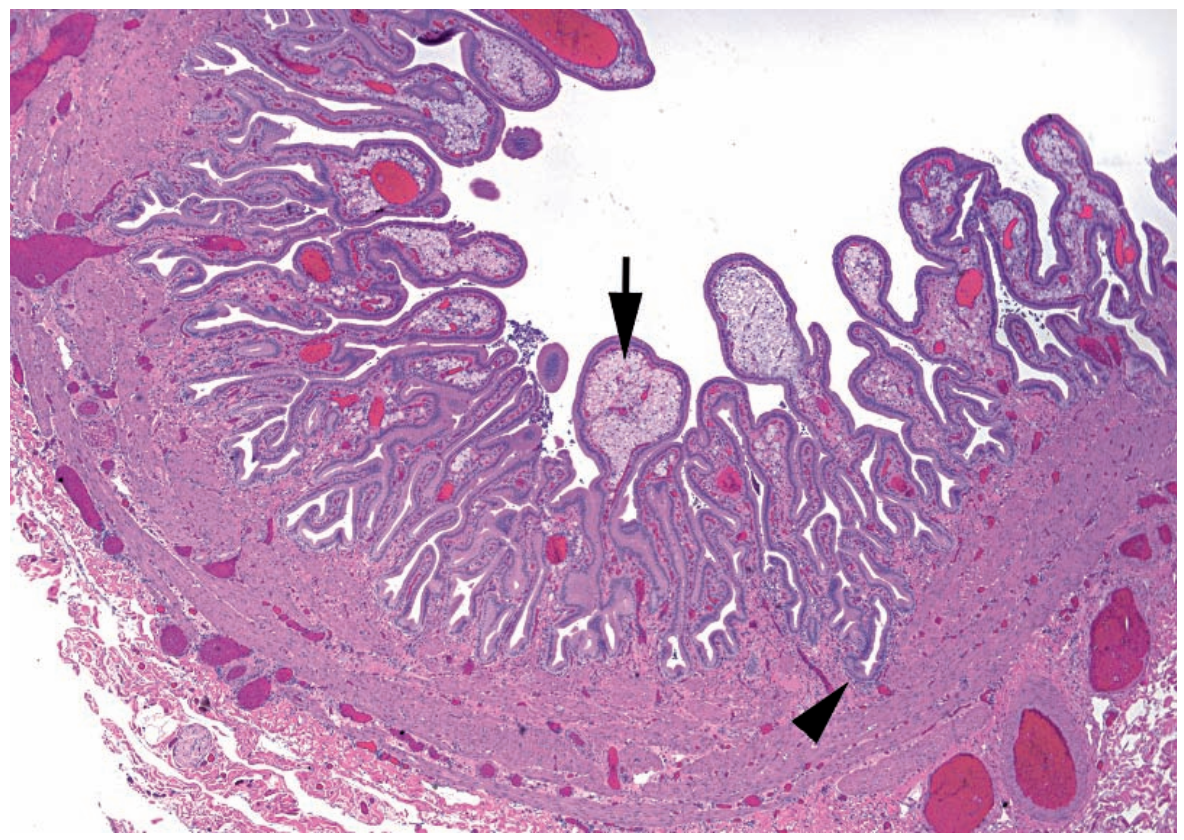

24

Q

A

Appendicitis.

Arrow: Residual colonic mucosa

Arrowhead: Fibrinopurulent debris